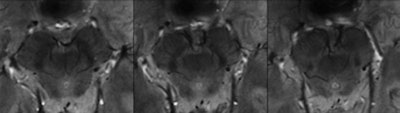

With ultrahigh-field MRI, the group was able to distinguish a three-layered organization of the substantia nigra, a crescent-shaped mass of cells in the midbrain. Based on abnormalities identified in the substantia nigra, the researchers correctly classified patients with Parkinson's disease with a sensitivity of 100% and specificity of 96.2%.

The two readers agreed in their description of a three-layered organization of the substantia nigra, and they were also able to distinguish Parkinson's patients from healthy subjects, the researchers found.

"In our study, 7-tesla MR targeted images of the midbrain provided a refined depiction of substantia nigra internal organization, which allowed for the identification of three tiers of different signal intensity along the posterior-anterior axis of the midbrain in healthy subjects," the authors wrote.